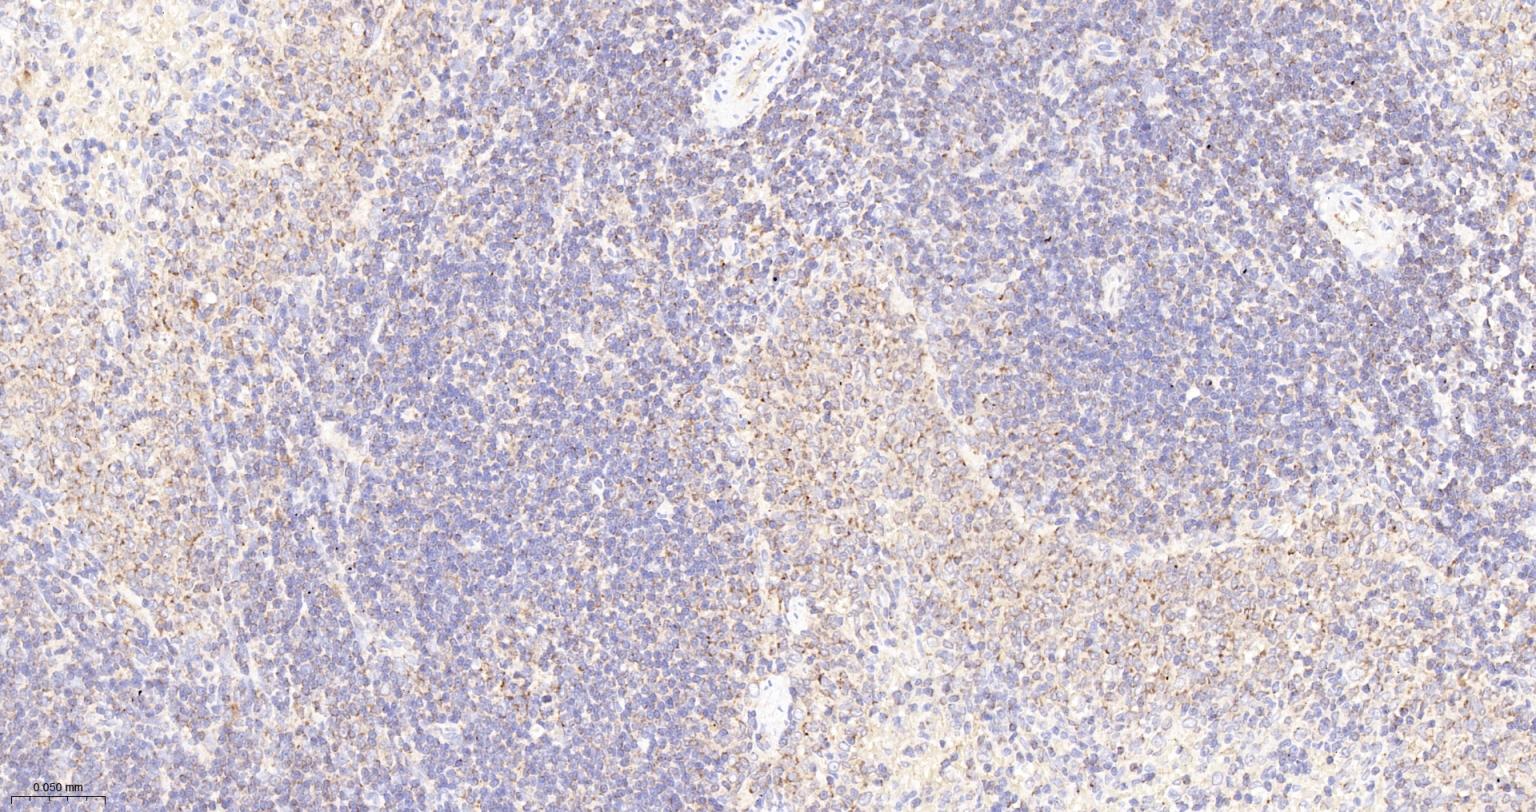

Paraformaldehyde-fixed, paraffin embedded Rat Thymus; Antigen retrieval by boiling in sodium citrate buffer (pH6.0) for 15 min; The section was incubated with Ubiquitin D Monoclonal Antibody, Unconjugated (bsm-61330R) at 1:200 overnight at 4°C, followed by conjugation to the bs-0295G-HRP and DAB (C-0010) staining.

Paraformaldehyde-fixed, paraffin embedded Mouse Thymus; Antigen retrieval by boiling in sodium citrate buffer (pH6.0) for 15 min; The section was incubated with Ubiquitin D Monoclonal Antibody, Unconjugated (bsm-61330R) at 1:200 overnight at 4°C, followed by conjugation to the bs-0295G-HRP and DAB (C-0010) staining.

Paraformaldehyde-fixed, paraffin embedded Rat Spleen; Antigen retrieval by boiling in sodium citrate buffer (pH6.0) for 15 min; The section was incubated with Ubiquitin D Monoclonal Antibody, Unconjugated (bsm-61330R) at 1:200 overnight at 4°C, followed by conjugation to the bs-0295G-HRP and DAB (C-0010) staining.

Paraformaldehyde-fixed, paraffin embedded Mouse Spleen; Antigen retrieval by boiling in sodium citrate buffer (pH6.0) for 15 min; The section was incubated with Ubiquitin D Monoclonal Antibody, Unconjugated (bsm-61330R) at 1:200 overnight at 4°C, followed by conjugation to the bs-0295G-HRP and DAB (C-0010) staining.